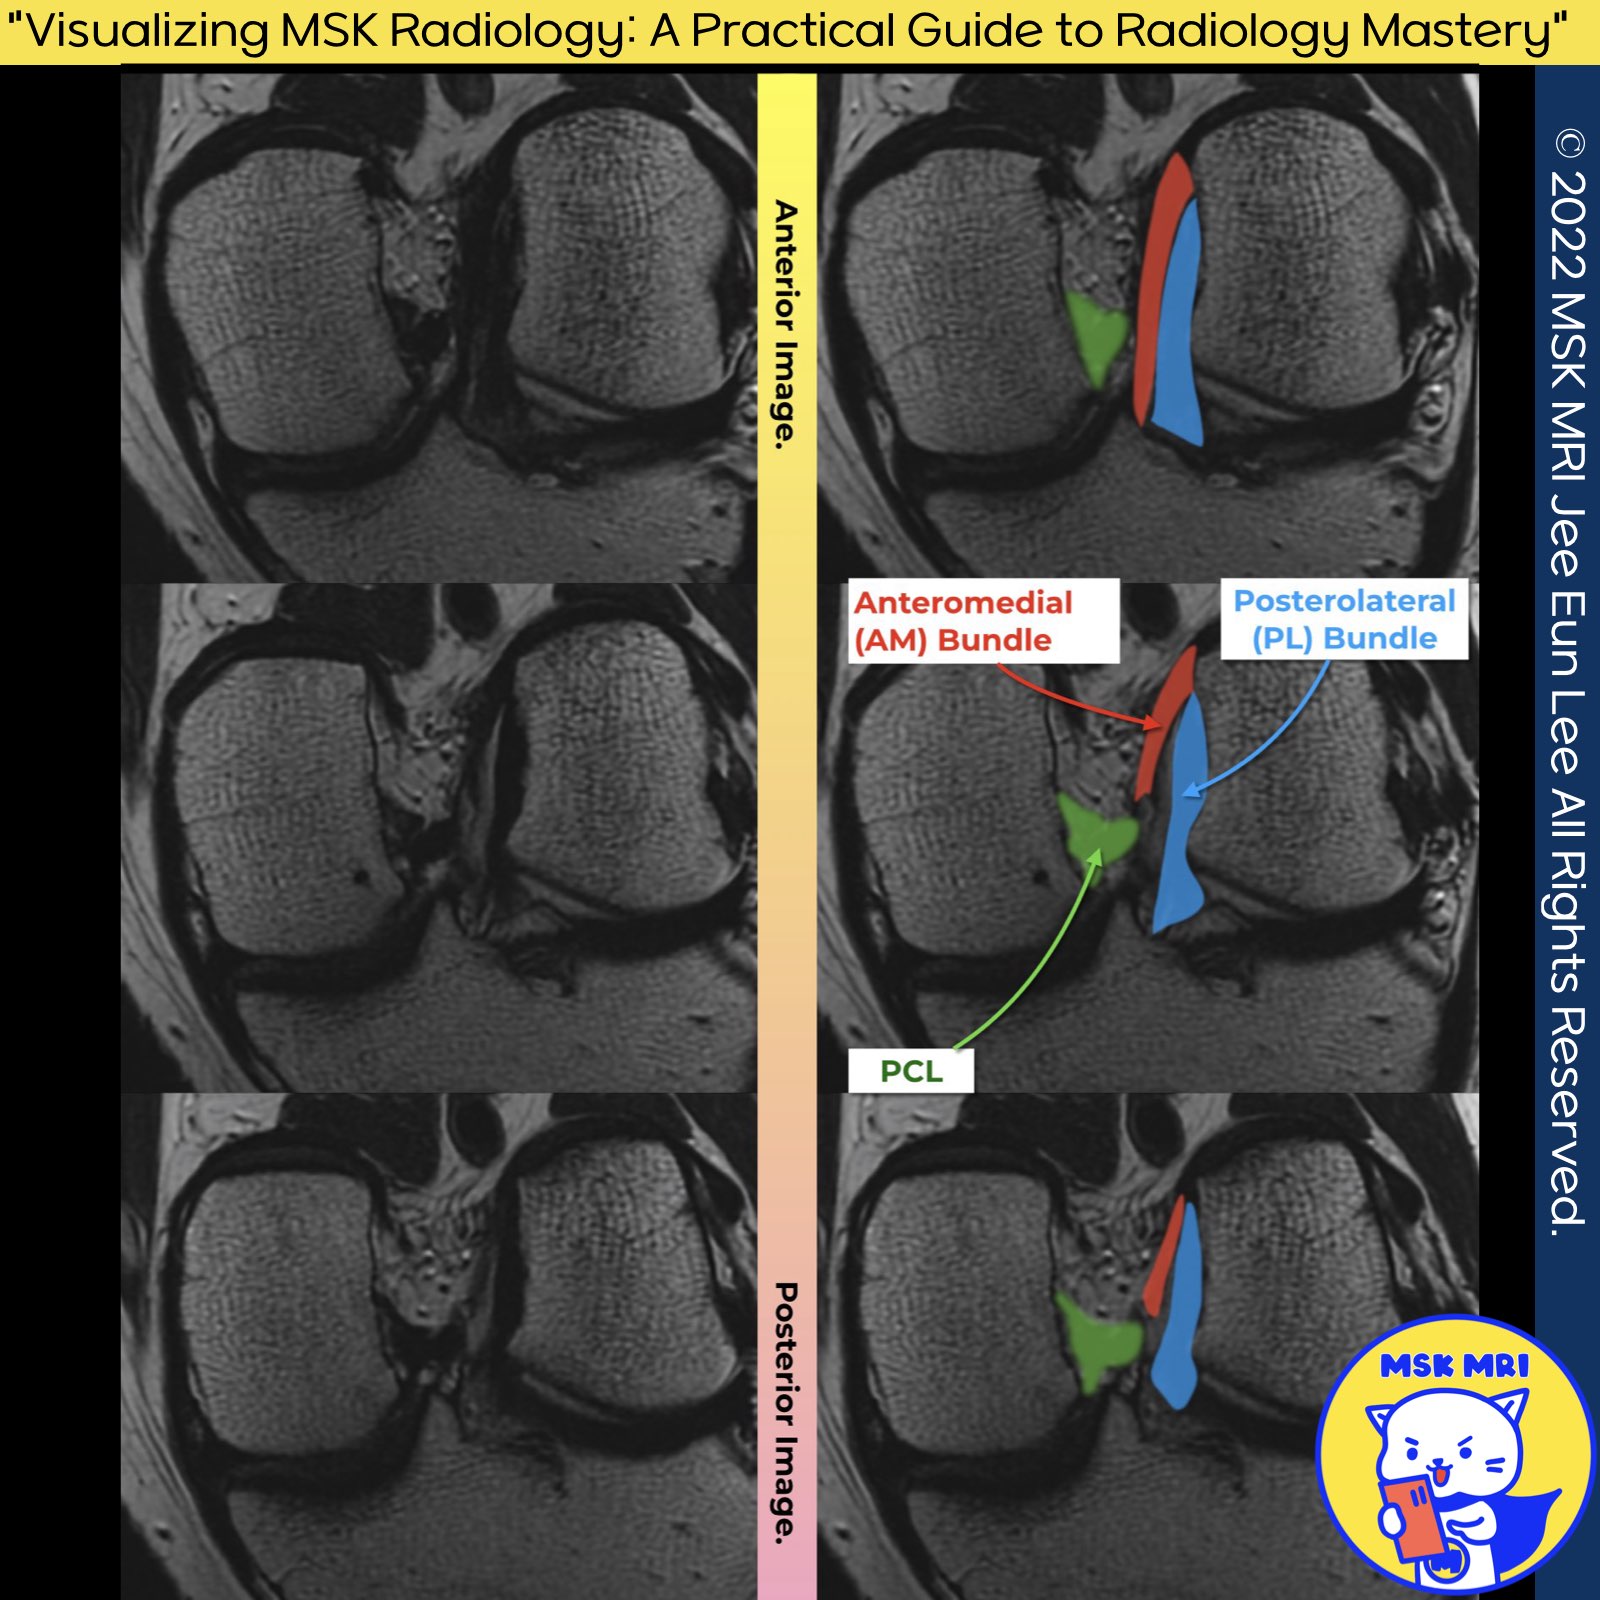

Normal ACL Visualization on Oblique Coronal Images

Oblique coronal imaging techniques, specifically tailored to align with the longitudinal axis of the Anterior Cruciate Ligament (ACL) or the roof of the intercondylar notch, play a crucial role in the depiction of the different components of the ACL and allow for complete visualization of the ACL.

| (Fig 2-A.04) Normal ACL on coronal images, anteromedial and posterolateral bundles of ACL (0) | 2024.02.16 |